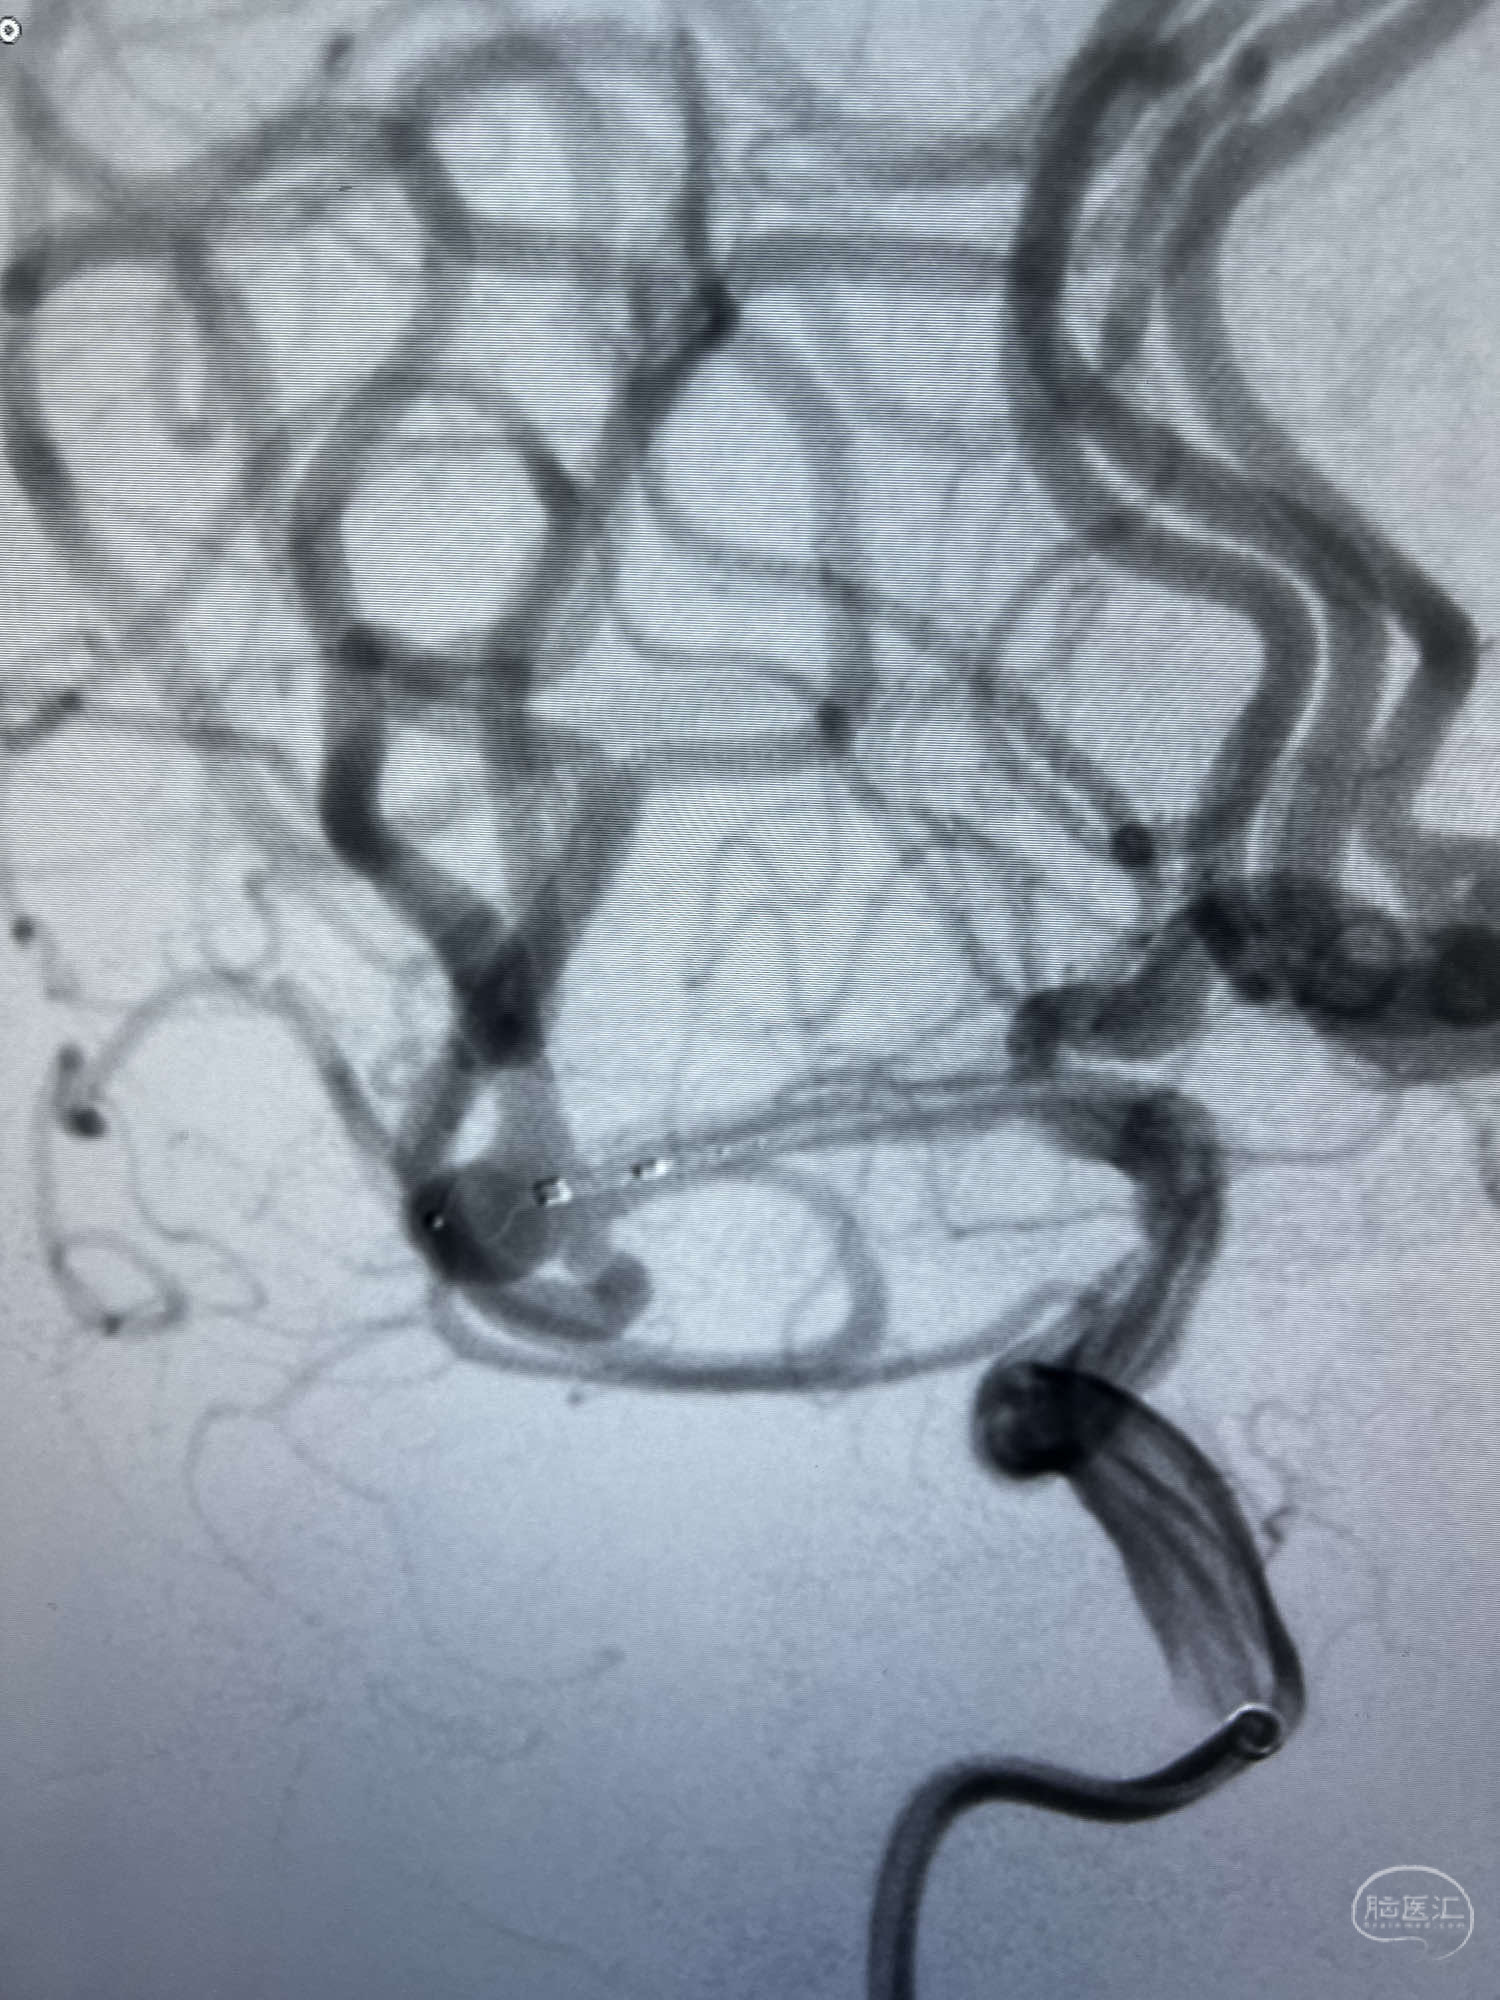

DSA示:左侧颈内动脉眼动脉段以远闭塞,后交通动脉开放,椎基底动脉通过后交通动脉代偿左侧大脑中动脉区域,右侧发出双侧大脑前动脉,右侧大脑中动脉M1末端宽颈动脉瘤,大小约4.3mmx4.6mm。

WEB瘤内扰流装置5mmx3mm经过“种子、萌芽、开花”三个阶段,打开后良好贴壁,动脉瘤内血液滞留,载瘤动脉通畅。WEB一步到位,通过瘤内扰流的方式起到栓塞动脉瘤的作用,避免了应用支架保护分支血管,简化了操作步骤,降低了术中血栓及出血的风险。